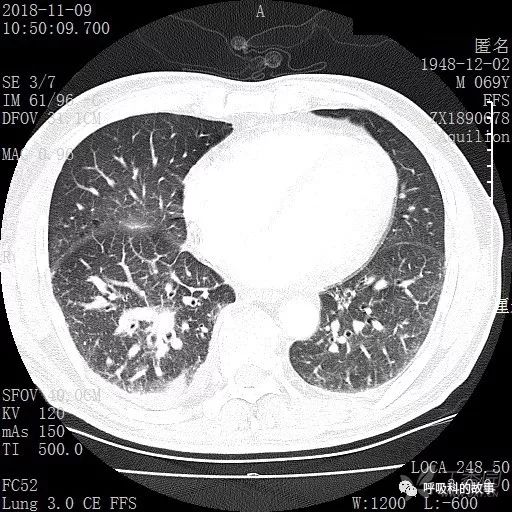

胸部增强CT示右肺门占位伴远端阻塞性肺炎,纵膈、右肺门、右侧颈根部、右侧腋下及肝门部肿大淋巴结。两侧胸腔少量积液。

肺窗CT